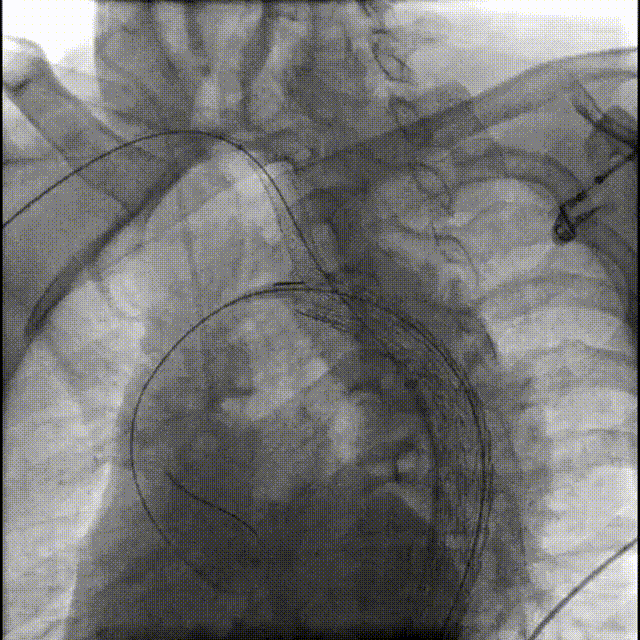

3.术中造影

gore医疗怎么样「胸有乾坤」释半功倍 得心应手——GORE®TAG® 可主动调控胸主动脉覆膜支架治疗B型主动脉夹层病例分享 复旦大学附属中山医院_https://www.jmylbn.com_新闻资讯_第8张

支架放置前内脏区造影

gore医疗怎么样「胸有乾坤」释半功倍 得心应手——GORE®TAG® 可主动调控胸主动脉覆膜支架治疗B型主动脉夹层病例分享 复旦大学附属中山医院_https://www.jmylbn.com_新闻资讯_第9张

支架放置后内脏区造影